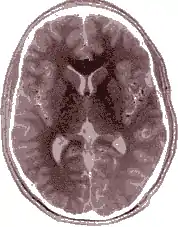

Le cerveau, bien que grossièrement symétrique d'un point de vue morphologique, est en réalité latéralisé tant du point de vue de certains détails anatomiques que sur le plan fonctionnel. On parle d'asymétrie cérébrale. Les deux hémisphères ne jouent pas un rôle identique : d'une part, en raison de la décussation des voies nerveuses, chaque hémisphère traite les informations en provenance et à destination de la moitié contralatérale du corps ; d'autre part, dans le domaine particulier du langage, il y a en général dominance de l'hémisphère gauche sur le droit.

Être latéralisé est une caractéristique des animaux qui se servent préférentiellement d'une seule main : c'est être gaucher ou droitier. Le fait d'être habile des deux mains est l'ambidextrie. Le cerveau humain (et à un moindre degré celui des autres vertébrés) est anatomiquement à peu près symétrique de sorte qu'un des deux hémisphères est symétrique de l'autre hémisphère. Cependant, il existe une importante dissymétrie fonctionnelle : chaque hémisphère prend en charge certaines tâches qui lui sont peu ou prou spécifiques ; on parle de spécialisation hémisphérique. Dans le cas des sujets qui sont droitiers homogènes (droitiers pour la main, le pied, l’œil et l'oreille), l'hémisphère gauche a un rôle essentiel pour les gestes précis, intentionnels, bien catégorisés ; on dit qu'il s'agit de l'hémisphère digital. L'autre hémisphère plus spécialisé dans la gestion du corps au service des intentions visées par l'hémisphère digital, gère les données plus globales, plus imagées ; il est qualifié d'hémisphère « analogique ».